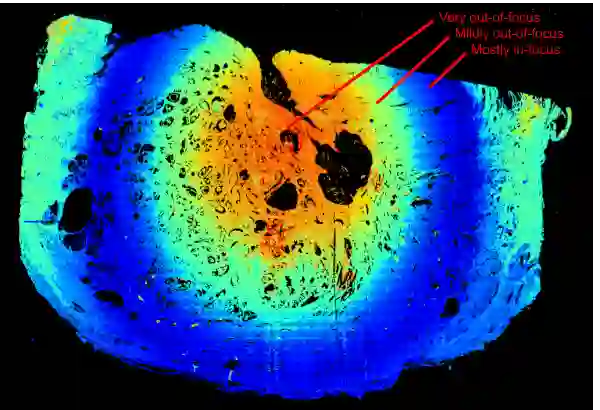

生物组织切片上的有趣失焦模式示例:(蓝色区域是模型识别的对焦区域,而以黄色、橙色或红色突出显示的区域则为失焦区域) 中心坚硬的“石头”将周围的生物组织引起的,导致了此处的焦点渐变(用同心圆表示:红色/橙色的失焦区域周围是轻微失焦的绿色/青色区域,然后是蓝色的聚焦环形区域)